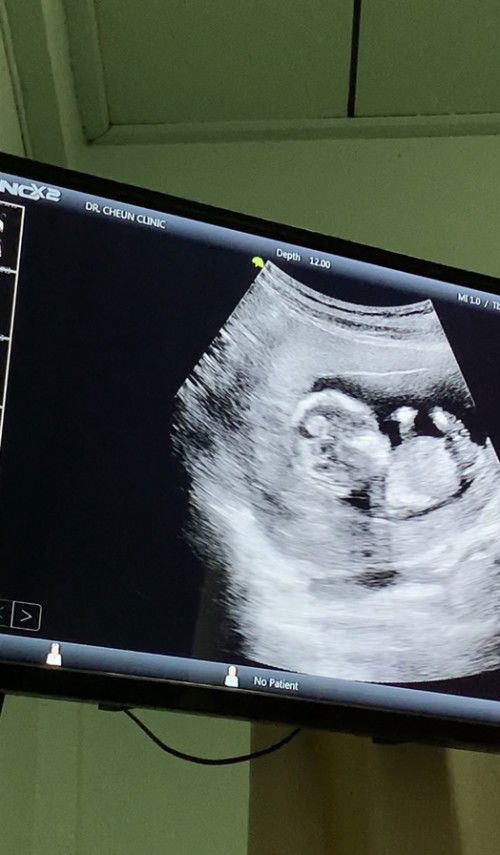

น้อง14วีค4วัน อัลตราซาวด์2มิติ น้องหัวโตแบบนี้ปกติไหมคะ กังวลมากค่ะแม่ๆท่านไหนพอทราบบ้างคะ ว่าแบบนี้น้องปกติไหม

#ท้องแรกค่ะ #ขอคำแนะนำหน่อยค่ะ #ขอบคณุสำหรับคำตอบค่ะ